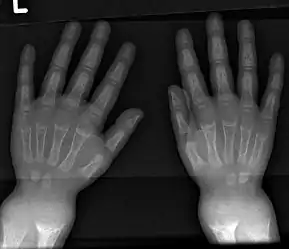

An X-ray or radiograph of an advanced patient with rickets tends to present in a classic way: the bowed legs (outward curve of long bone of the legs) and a deformed chest. Changes in the skull also occur causing a distinctive "square headed" appearance known as "caput quadratum".[14] These deformities persist into adult life if not treated. Long-term consequences include permanent curvatures or disfiguration of the long bones, and a curved back.[15]

- Radiography typically show widening of the zones of provisional calcification of the metaphyses secondary to unmineralized osteoid. Cupping, fraying, and splaying of metaphyses typically appears with growth and continued weight bearing.[40] These changes are seen predominantly at sites of rapid growth, including the proximal humerus, distal radius, distal femur and both the proximal and the distal tibia. Therefore, a skeletal survey for rickets can be accomplished with anteroposterior radiographs of the knees, wrists, and ankles.[40]